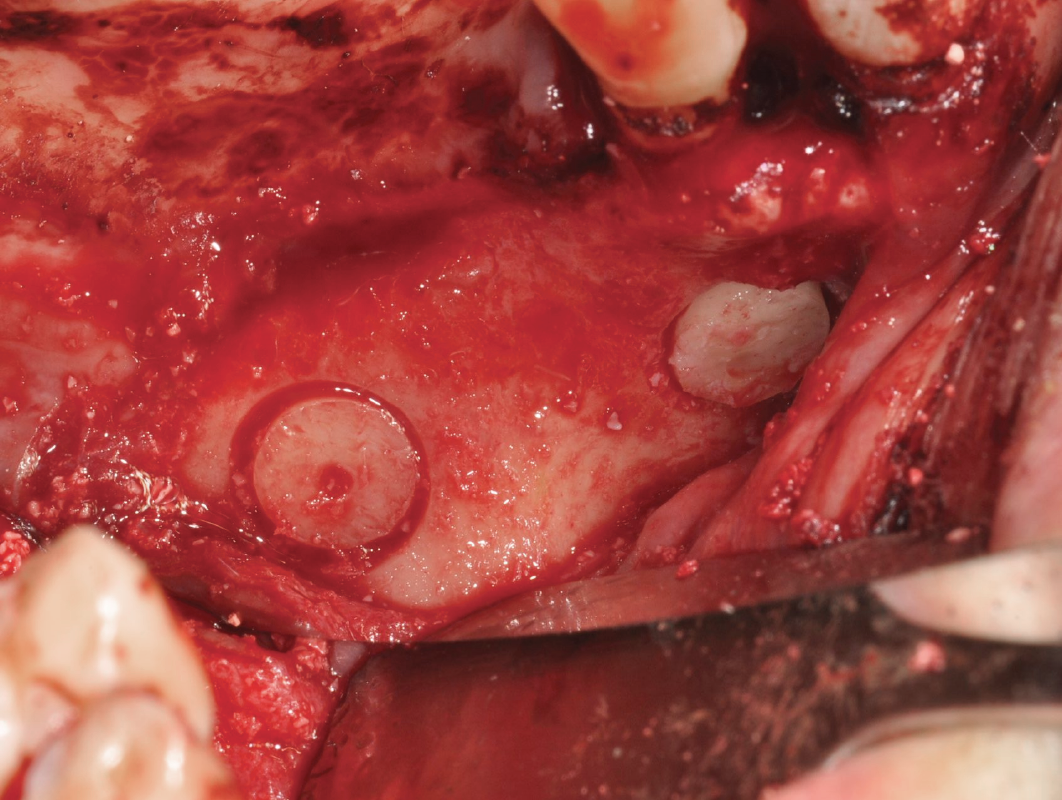

THE TECHNIQUES PIT STOP – MASTERING SINUS AUGMENTATION

Lateral Window Approach – The Formula 1

This approach requires precision, just like a well-timed drift. We’ll break down each step to make your technique smooth and controlled.

Lateral Window Approach – The Formula 1

This approach requires precision, just like a well-timed drift. We’ll break down each step to make your technique smooth and controlled.

01

OFF-ROADING – HANDLING COMPLEX CASES

The Terrain Gets Tougher

When sinus anatomy is severely atrophic, it’s like driving off-road. We’ll cover modifications to handle the “rougher terrain” of complex sinus cases.